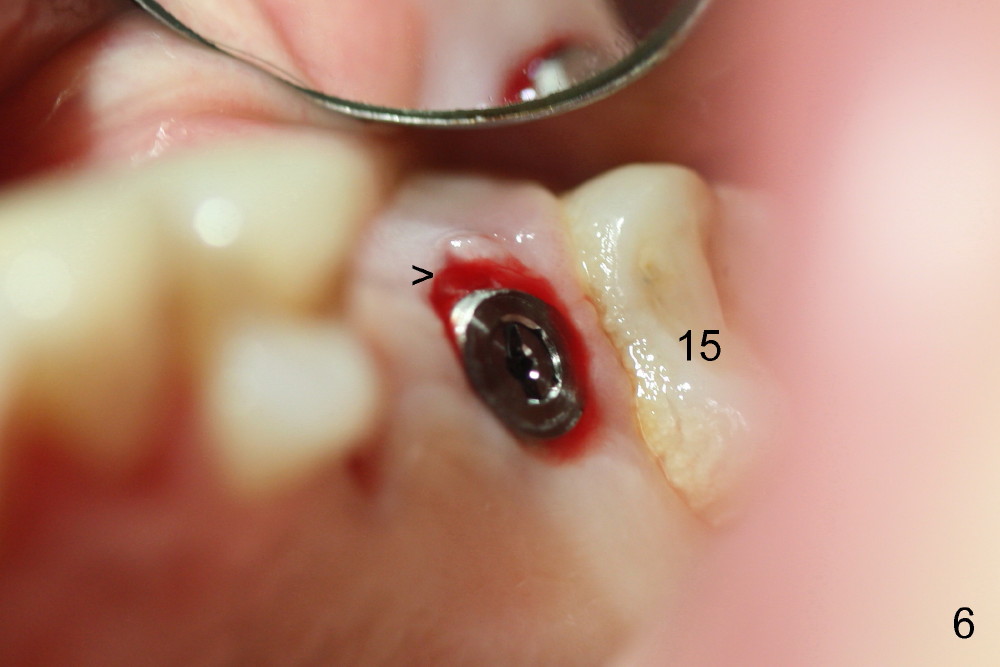

The patient returns for #13,14 implant placement. The ridge appears to be wide buccolingually (Fig.1 mirror view). A 4 mm tissue punch is used for access at the sites of #13 and 14. Osteotomy is initiated by using 3 mm trephine bur at the depth of 4 mm at both sites; 2 mm pilot drill is used to continue osteotomy at 8 mm deep at the site of #13. Sinus lift is accomplished by using tapered osteotomes 2,3 mm 6 mm deep, followed by 4.5x11 mm tap (Fig.2 T); 2 mm pilot drill (P) is reinserted into #13 osteotomy site with inadvertently penetrating the sinus floor. When the tap is removed from the site of #14, the sinus membrane is also found to be perforated. The sinus membrane at both sites is repaired by insertion of collagen dressing before bone graft. A 4x11 mm one-piece implant is placed at the site of #13 slowly hoping that it does not re-perforate the sinus membrane (Fig.3 O). Due to limited restorative height, the abutment portion of the one-piece is expected to be trimmed (Fig.4 O). In case of implant complication or failure, the implant may be difficult to be removed. Therefore the implant at the site of #14 is two piece one (Fig.4,5 I/A, 5x11 and 4x3 mm, respectively). The insertion torques for #13 and 14 are 35/40 and >60 Ncm. Immediate provisionals are canceled mainly because of patient's inability to open wide for long. Perio dressing is placed instead after adjustment of the height of the abutments. The patient experiences one episode of light nasal hemorrhage a few hours postop. Although the patient takes Amoxicillin for 1 week periop, the implant at the site of #13 dislodges 1 months postop (Fig.5). Immediate re-placement with a larger 2 piece one is canceled because of mild infection mesiobuccal to the implant at the site of #14 (Fig.6 >). Exploration around the latter implant reveals possible thread exposure in a small area. After copious irrigation with normal saline, Arestin is placed. Two months post exfoliation, the site is re-entered (Fig.7,8). There is a lingual defect. Osteotomy is initiated as buccal as possible. A 4.5x11 mm tapered tap penetrates the sinus floor without tearing the membrane (Fig.9). The same-sized implant is placed (25/30 Ncm) with sinus lift (Fig.10 *). The lingual defect is bone grafted. There is dehiscence lingually 7 days postop (Fig.11). Impression for final restoration is taken 1.5 months postop because of pending wedding. The crown has been in function for 2.5 months.